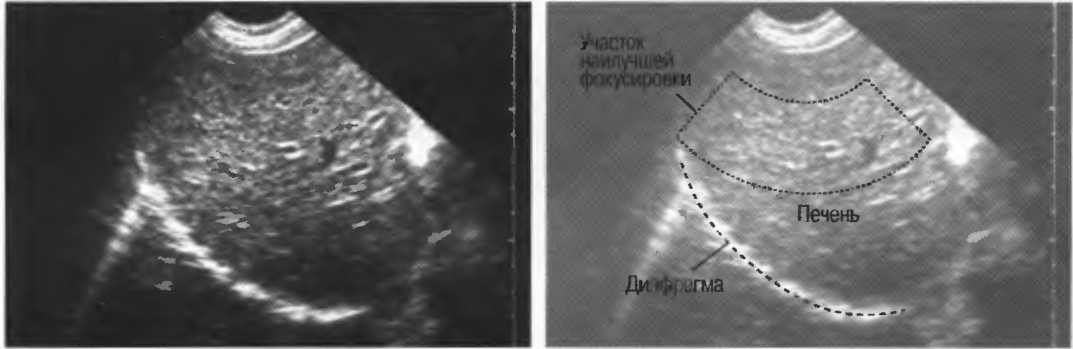

Фокусировка может осуществляться линзами, зеркалами или электронным путем в многоэлементных датчиках. Как узко направленный пучок света более четко показывает объект, чем более рассеянный, несфокусированный поток, так и фокусированный ультразвук дает более тонкий срез ткани, в результате чего изображение получается более детальным. Для получения наилучшего результата необходима фокусировка на той глубине, которая наилучшим способом соответствует поставленной клинической задаче. Для аппаратов общего назначения это означает использование специальных датчиков для различных целей и, при необходимости, использование программы фокусировки аппарата (рис. 3).

Рис.3. Центр изображения в фокусе, в то время как периферия — нет.

Различные варианты фокусировки

Многие трансдьюсеры имеют фиксированный фокус. Многоэлементные трансдьюсеры, например линейные или конвексные, а также аннулярные секторные имеют электронно задаваемое фокусное расстояние, устанавливаемое на требуемую глубину. Тем не менее многие трансдьюсеры имеют фиксированное фокусное расстояние: только аннулярные секторные датчики имеют электронную фокусировку во всех плоскостях. Регулирование фокусировки обеспечивает узкий акустический поток и более тонкую плоскость среза: это дает более высокую разрешающую способность и более четкое изображение с большей информацией.